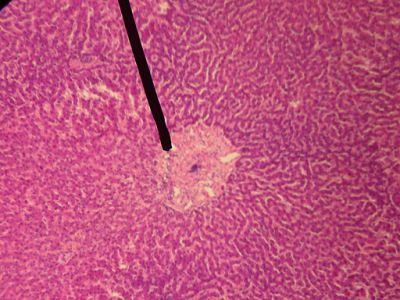

This is a histology slide of the liver. The pointer is on the central vein.